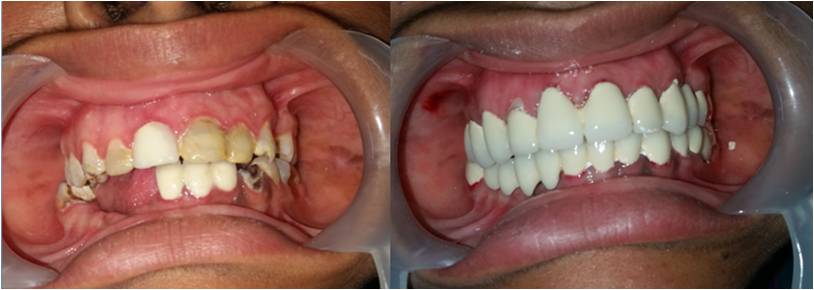

We are a team of 3 certified dentists specialised in offering the best dental treatments in town. With adequate experience of over 17 years, we have mastered the skills of offering the best solutions with the latest technologies.At Sri Durga Specialty Dental Clinic, we are dedicated to providing top-quality dental care in a comfortable and friendly environment. Our team of experienced dentists and staff use the latest technology and techniques to ensure the best outcomes for our patients. From routine check-ups to advanced dental procedures, we offer a comprehensive range of services to meet all your dental needs. We pride ourselves on our patient-centered approach, focusing on personalized care and building lasting relationships.

Cosmetic Dentistry

Dr. T. Harshavardhan Reddy, MDS, is an esteemed Oral Physician and Implantologist committed to delivering exceptional dental care. With extensive expertise and a patient-focused approach, he ensures top-quality treatment for all.